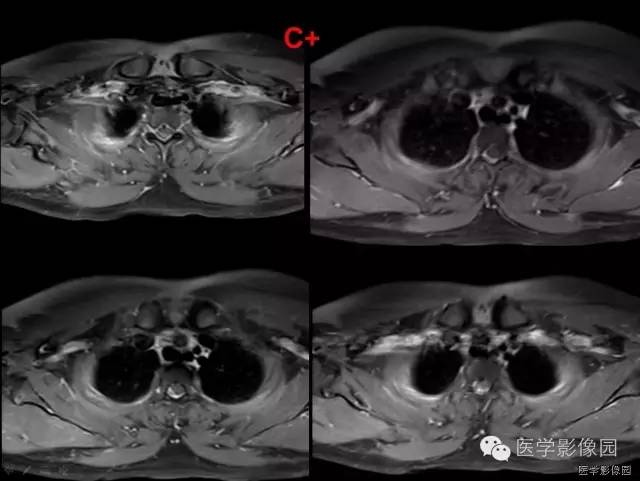

MRI是SSEH最有效的诊断方法,易于发现微小的出血灶,可以准确反映病灶的大小、形态、部位及与周围组织的关系;

根据病变的信号不同,可与炎症和肿瘤等病变相鉴别,明确血肿性质及推断出血时间,鉴别血肿分期,结合临床表现决定治疗方案。

硬膜外脓肿、转移瘤和淋巴瘤与急性期的硬膜外血肿影像学表现很相似,增强扫描对于鉴别诊断非常重要。

脓肿周围脓壁可出现明显环行强化,转移瘤和淋巴瘤均表现为显著较均匀强化,而SSEH在急性期强化不明显; 硬膜下血肿在临床上出现的概率远低于SSEH,多位于脊髓的腹侧面,SSEH表现为脊髓受压,一般不包绕脊髓,而硬膜下血肿,可以包绕脊髓或马尾,由于不受硬膜限制,没有硬膜移位,表面常不规则;海绵状血管瘤由于反复出血可致含铁血黄素沉积,在T2W I上病灶周边可见低信号带,易与SSEH区别。